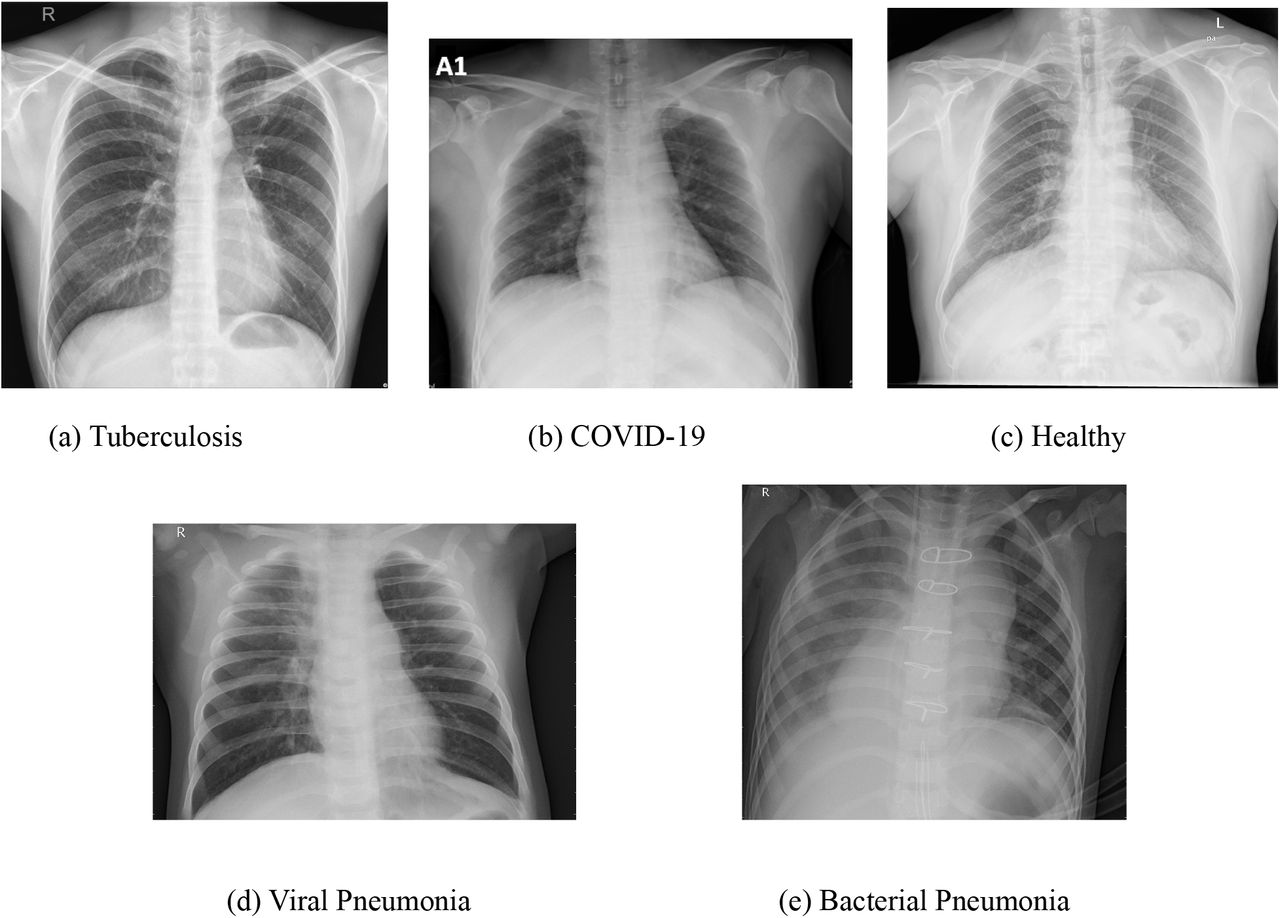

Zapalenie płuc na zdjęciu RTG objawia się przede wszystkim zacienieniami miąższu płucnego, które radiolog ocenia pod kątem rozległości i charakteru. W typowym obrazie bakteryjnego zapalenia płuc, takiego jak pneumokokowe, dominuje konsolidacja – homogeniczne zacienienie obejmujące cały płat płucny, np. dolny prawy (u 40-50% pacjentów wg badań z lat 2018-2022 w European Respiratory Journal). Nacieki zapalne tworzą „pianę” lub mleczne obszary, kontrastujące z przeziernością zdrowego miąższu. Wczesne stadia mogą przypominać mgłę (zacienienia szkliste, ground-glass opacities), szczególnie w wirusowych formach, jak COVID-19, gdzie wykrywalność sięga 60-80% na standardowym RTG klatki piersiowej. Radiolog szuka też poszerzenia naczyniowego lub linii Kerleya, wskazujących na obrzęk śródmiąższowy. Czy zawsze zapalenie płuc daje wyraźne zmiany na zdjęciu RTG? Nie – u 10-20% chorych obraz bywa subtelny, przede wszystkim w odmieńcach u dzieci lub starszych.

- Homogenna konsolidacja płata: klasyka pneumonii bakteryjnej, np. Streptococcus pneumoniae.

- Zacienienia szkliste (GGO): wirusowe etiologie, jak RSV lub SARS-CoV-2 (widoczne u 75% hospitalizowanych).

- Naciek z air bronchogramem: potwierdza zapalenie miąższowe.

- Drobne nacieki guzkowate: atypowe zapalenie, np. Mycoplasma pneumoniae.

- Rozlane zacienienia interstycjalne: wczesna faza lub grzybicze.

Bakteryjne zmiany są najczęściej jednostronne i ostre, z wyraźnym air bronchogramem – widocznymi oskrzelami wypełnionymi powietrzem na tle zacienionego miąższu. Wirusowe zapalenie płuc, np. wywołane grypą lub RSV, prezentuje się inaczej: dominują międzypłatowe nacieki o charakterze międzywrzodowym, rozproszone obustronnie. Te ziarniste lub siateczkowate zmiany zajmują oba płuca w 60-90% przypadków, bez homogennej konsolidacji.

Wirusowe postacie zapalenia płuc na zdjęciach rentgenowskich klatki piersiowej często przypominają obrzęk płucny, z perihilarnymi smugami i zagęszczeniami w dolnych polach. Bakteryjne zapalenie płuc wykazuje z kolei szybką ewolucję – konsolidacja może ustąpić po 48-72 godzinach antybiotykoterapii, co potwierdza RTG kontrolne. Frazy takie jak charakterystyczne cechy bakteryjnego zapalenia płuc w rentgenie pomagają radiologom w szybkim różnicowaniu.

Obraz radiologiczny wirusowego zapalenia płuc bywa subtelny, z hiperaeracją płuc i brakiem płynu w jamie opłucnowej, co odróżnia je od bakteryjnych ropni. W badaniach z lat 2010-2020, np. te publikowane w Radiology, aż 75% wirusowych przypadków wymagało potwierdzenia tomografią komputerową z powodu niejednoznaczności RTG. Te różnice między bakteryjnym a wirusowym zapaleniem płuc w obrazie rentgenowskim wpływają na dobór terapii.